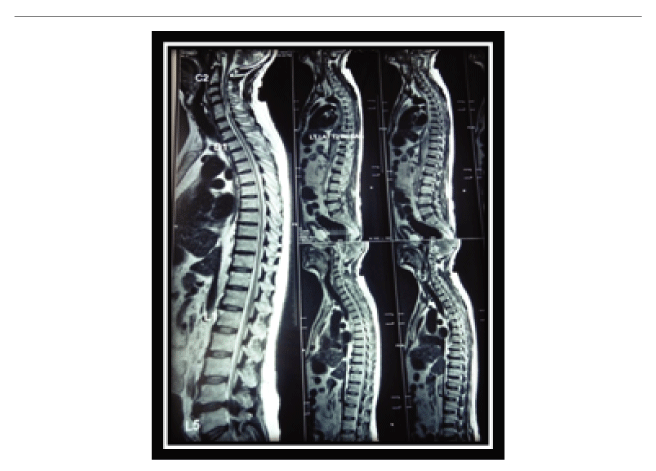

磁共振成像(MRI)显示右侧脑桥急性梗死,两侧额顶叶白质区少量缺血灶,左侧乳突炎改变(图1)。血管造影显示右侧椎动脉发育不良,左侧大脑前动脉A1段血流不可见,两侧后交通动脉发育不良。全脊柱MRI显示C3-5和L5-S1节段轻度退行性椎间盘病变,矢状面中部C5节段脊髓信号强度改变区(图2)。

图2:脊髓MRI显示C3-5和L5-S1节段轻度退行性椎间盘病变,C5-6椎间盘切除和融合